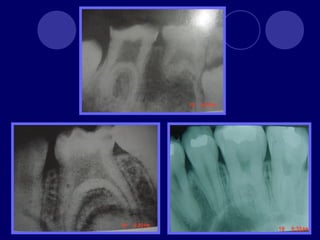

TAURODONTISMO  cuerpo deldiente se alarga, raíces cortas, furca se desplaza hacia apical, cámara pulpar amplia en sentido apico-oclusal  Dx: radiográfico  Etiología retraso en la vaina radicular de hertwing en invaginarse horizontalmente, hasta que esta cerca del ápice.  Fx: 0.5 -5 %  Se asocia a Síndromes congénitos, con herencia ligada al sexo (Sx. Klinefelter)

 Se clasificaen tres según el grado de afectación y la extensión de la cámara pulpar:  Hipotaurodontismo: leve, la corona es 1/3 total del diente, el cuello -1/3, y la raíz -2/3  Mesotaurodontismo: la raíz se divide en el tercio medio apical, la cámara pulpar es más ancha que alta, 1/3 las tres porciones  Hipertaurodontismo: la raíz se divide en el tercio ápical o no se divide, la cámara pulpar es más alta que ancha. La corona 1/3, cuello 2/3.

DENS IN DENTE Dienteinvaginado, invaginación de las células del epitelio interno del órgano del esmalte. Más frecuente en dientes anteriores superiores, lateral, central, 2:1 Esmalte, dentina (cemento) Radiográfico